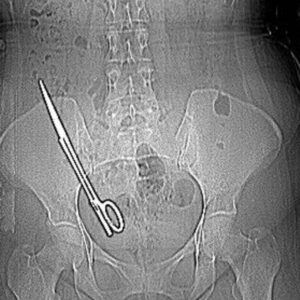

Doğuştan kalp hastalığı bulunan, ileri derecede kalp yetmezliği yaşayan 11 yaşındaki çocuk, kalbinin durduğu kritik anda uygulanan açık kalp cerrahisi sayesinde yeniden hayata döndürülerek sağlığına kavuştu Gaziantep’te yaşayan doğuştan aort kapak hastası Azat Enes Aslan, iki ay önce acil olarak Sağlık Bakanlığına ait uçak ambulansla İstanbul’daki Koşuyolu Yüksek İhtisas Eğitim...